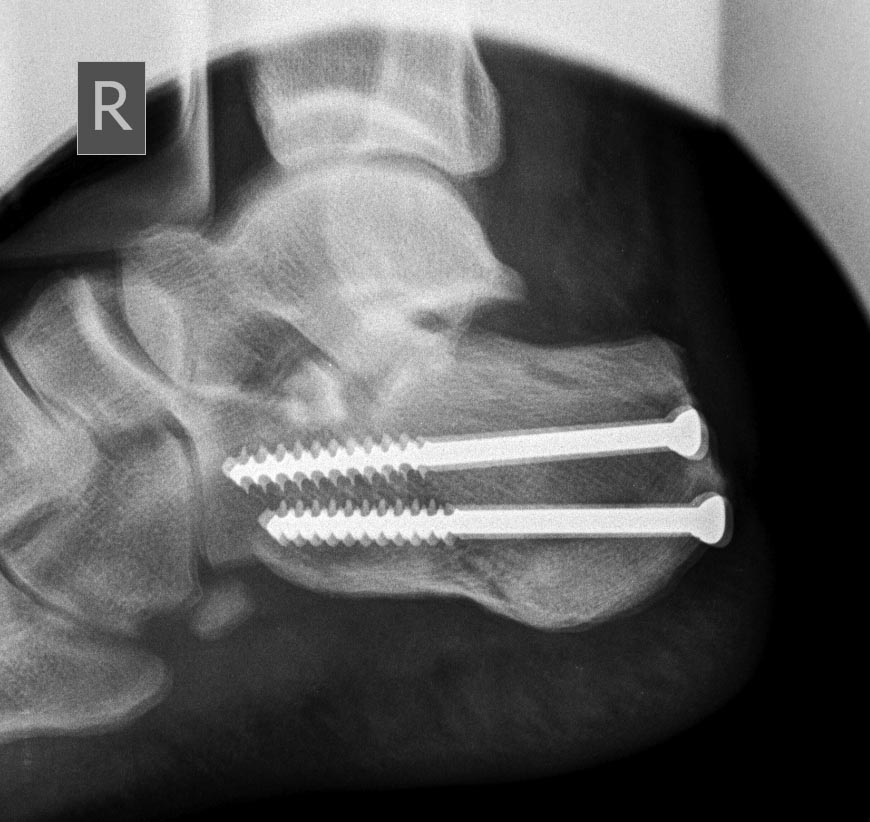

уважаемые коллеги ,помогите советом ,примерами.перелом пятки 4 мес назад

при дтп,синтез винтами.гипс носил около 3 мес ,нагрузка также через 3

мес(со слов пациента)в настоящий момент варусная деформация,толком

ходить на может,нагрузка на латеральну. полерхность пятки. латеральный

импиджмент.